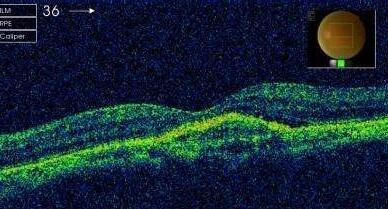

中渗